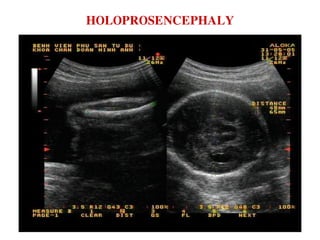

HOLOPROSENCEPHALY

NAÕO THAÁT DUY 1 + ÑOÀI THÒ BIEÁN DAÏNG

ÑOÀI THÒ BIEÁN DAÏNG